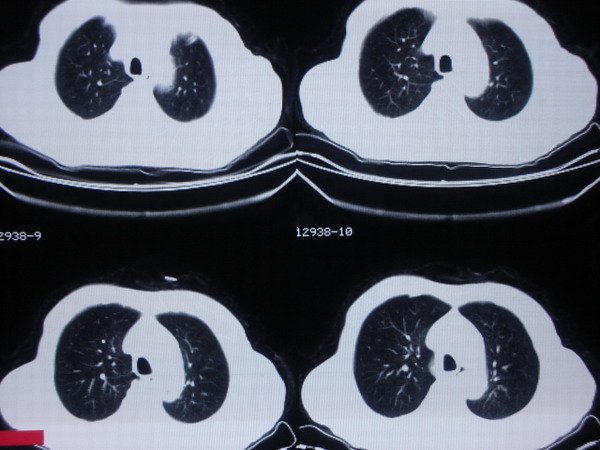

标题: CT5551:膀胱Ca术后 [打印本页]

标题: CT5551:膀胱Ca术后

考虑双肺转移瘤,肋骨应该是软骨钙化.

考虑双肺,肋骨转移

考虑膀胱癌两肺及肋骨转移。

肋骨未见破坏.左下肺炎症,右侧结节影密度太高,考虑钙化影.

考虑为双肺转移,肋骨考虑为软骨钙化影

有病史两肺多发小结节.还是首先考虑转移.5楼怀疑钙化.有病史还是要小心.什么病史引起的钙化?没发解释

支持膀胱癌术后肺转移。

支持膀胱ca术后肺部、肋骨转移。

支持膀胱癌术后肺转移,右侧肋骨末端不规则高密度影考虑为了软骨钙化。